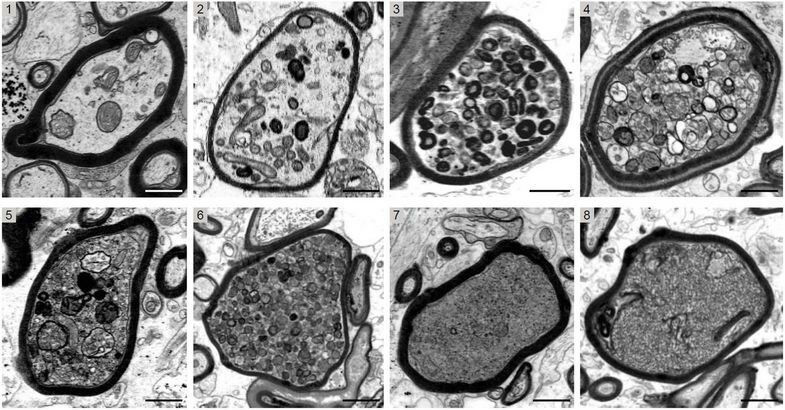

The image series shows cross-sectional electron micrographs of individual nerve fibers in MS brain biopsies. Axons sheathed with myelin (black rings) can be seen, showing increasingly severe damage from 1 to 8. The...

The image series shows cross-sectional electron micrographs of individual nerve fibers in MS brain biopsies. Axons sheathed with myelin (black rings) can be seen, showing increasingly severe damage from 1 to 8. The. Multiple sclerosis (MS) affects millions of people worldwide, and there is currently no cure for this disease of the central nervous system. Damage to the nerve fibres, also called axons, is responsible for the severity of MS in patients and for the course of the disease. And myelin, which is the protective layer around axons, plays a key role in this process. Researchers at Leipzig University and Max Planck Institute for Multidisciplinary Sciences in Göttingen have discovered that myelin, which was previously thought to be solely protective, can actually threaten the survival of the axons.